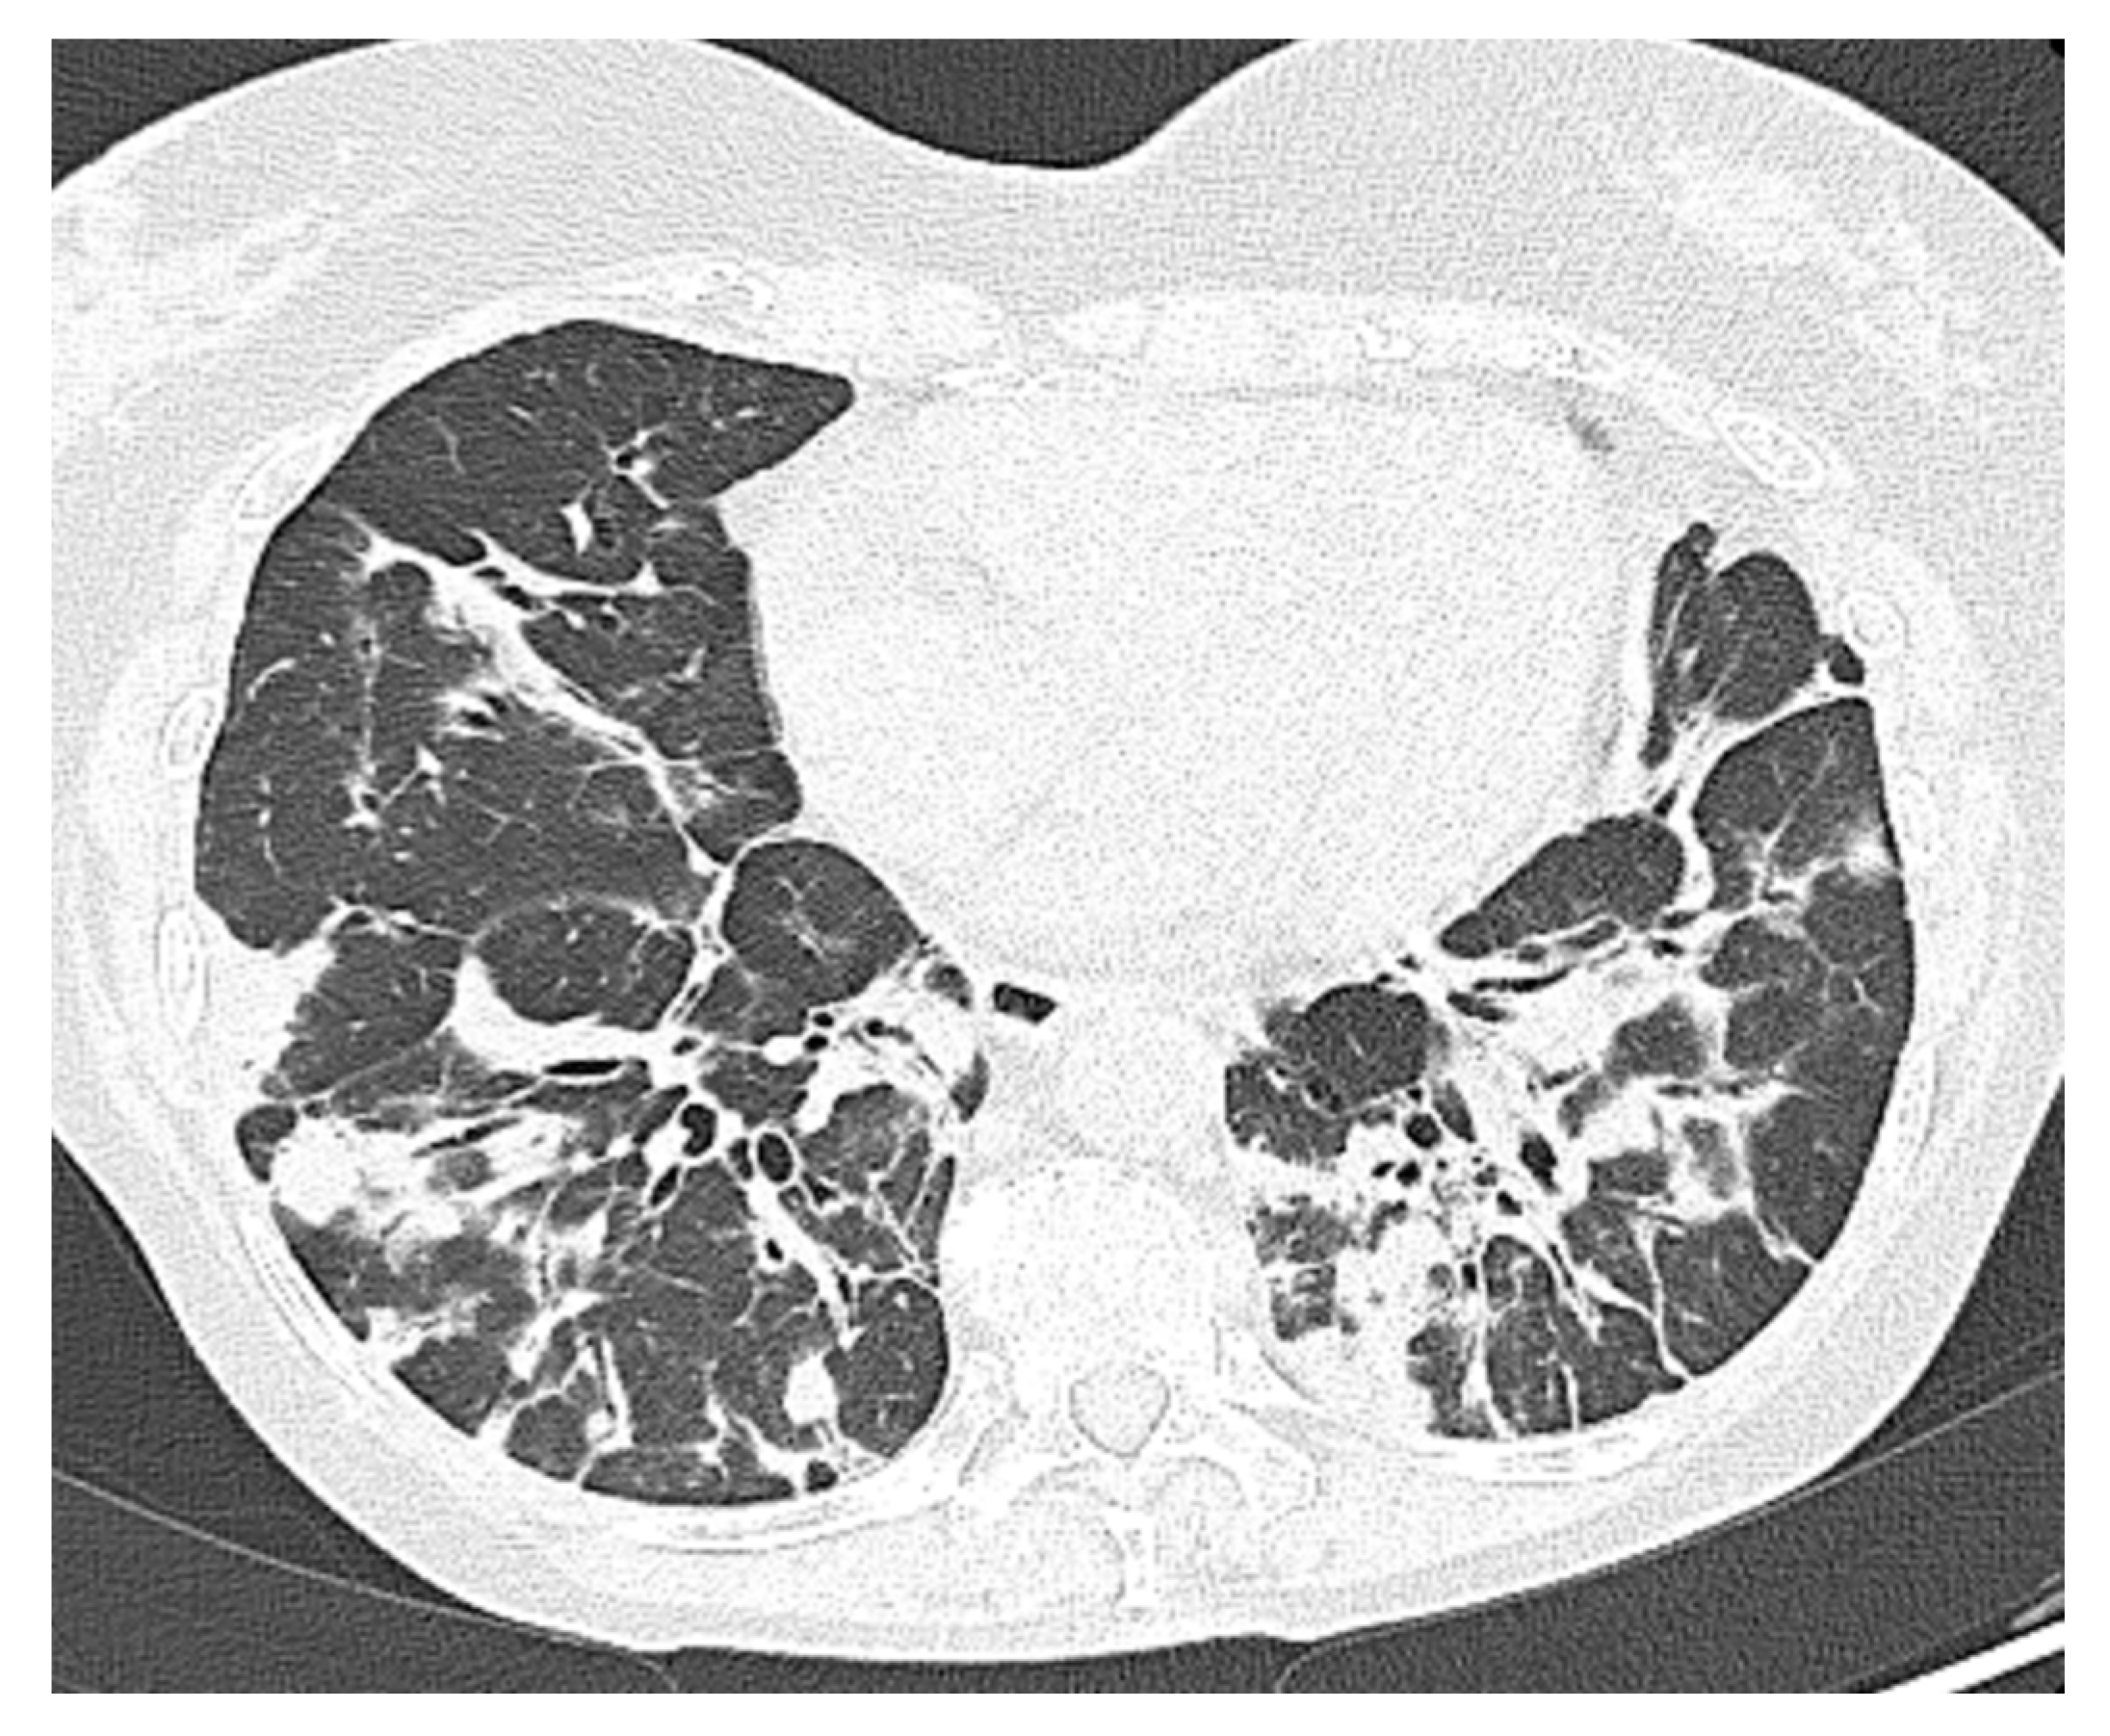

| Comorbidity | RA | Splenomegaly, bronchiectasis; recurrent viral infections | Hypertrophic cardiomyopathy; AF; CKD secondary to nephrolithiasis. C | Bronchiectasis; COPD; EBV-related NHL | GLILD; Bronchiectasis; colonization Aspergillus; Sjogren syndrome; CKD |

| Severity according to WHO classification | moderate | moderate | severe | severe | moderate |

| SARS-CoV-2 related pneumonia | yes | yes | yes | yes | no |

| O2 supplementation therapy needed | LFNC | LFNC | HFNC | HFNC | LFNC |